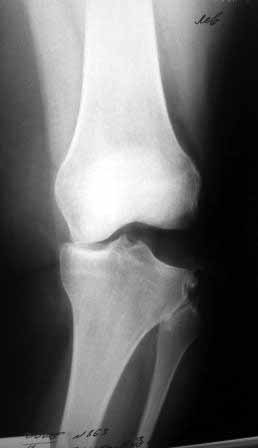

Сегодня на приеме была больная 27 лет, вес 120кг. Травма 7 лет назад - ДТП. Была ЧМТ, двухсторонний перелом пилона, обширные рваные раны бедер, голеней. Судя по нынешней картине - вывих левой голени.

Ходит практически не хромая, жалобы на неустойчивость голени при ходьбе. При стресс тестах - грубейшая несостоятельность связочного аппарата

коленного сустава. Хотелось бы услышать мнение о целесообразности пластического восстановления связок после столь длительного периода

нестабильности сустава.